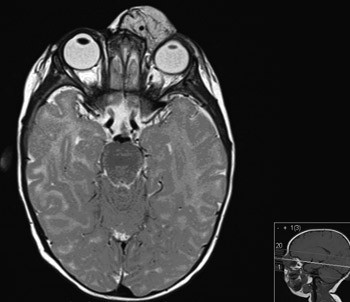

MR orbita viste en velavgrenset kontrastoppladende ekspansjon, forenlig med hemangiom (fig 2). Hemangiomet hadde bred kontakt med bulbus og m. rectus medialis med avflating av bulbus oculi. Det var ikke tegn til dyp infiltrasjon inn i orbita eller hemangiomkomponenter intrakonalt.